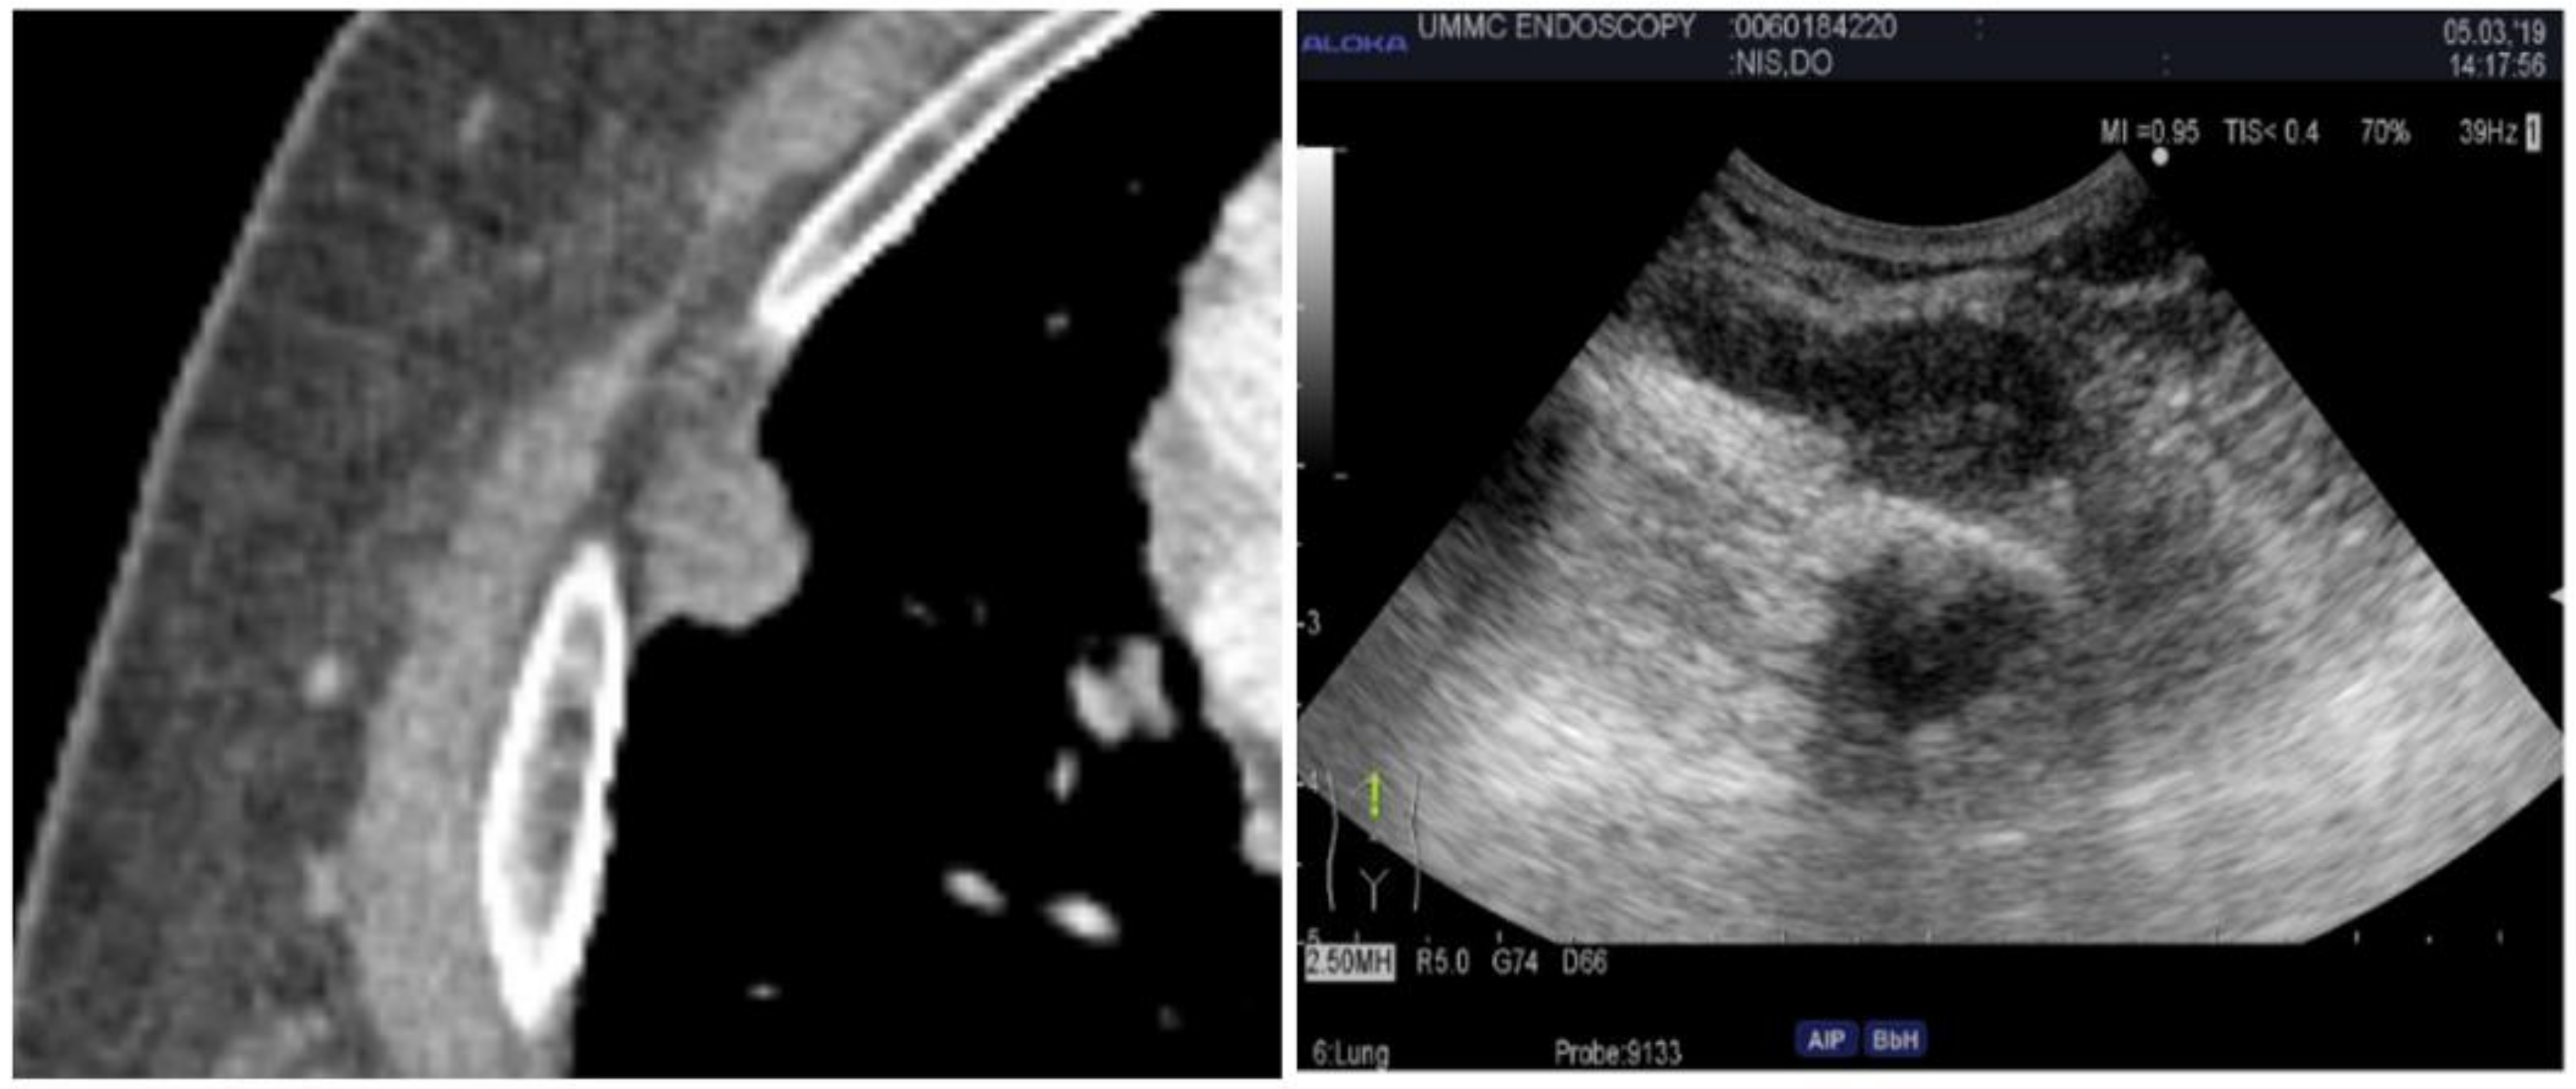

2.4. Endobronchial Ultrasound

2.5. Peripheral Ultrasound